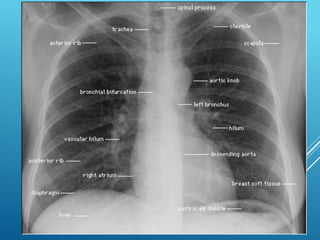

CXR CASE 1

 You suspect heart failure. What tests would you

order?